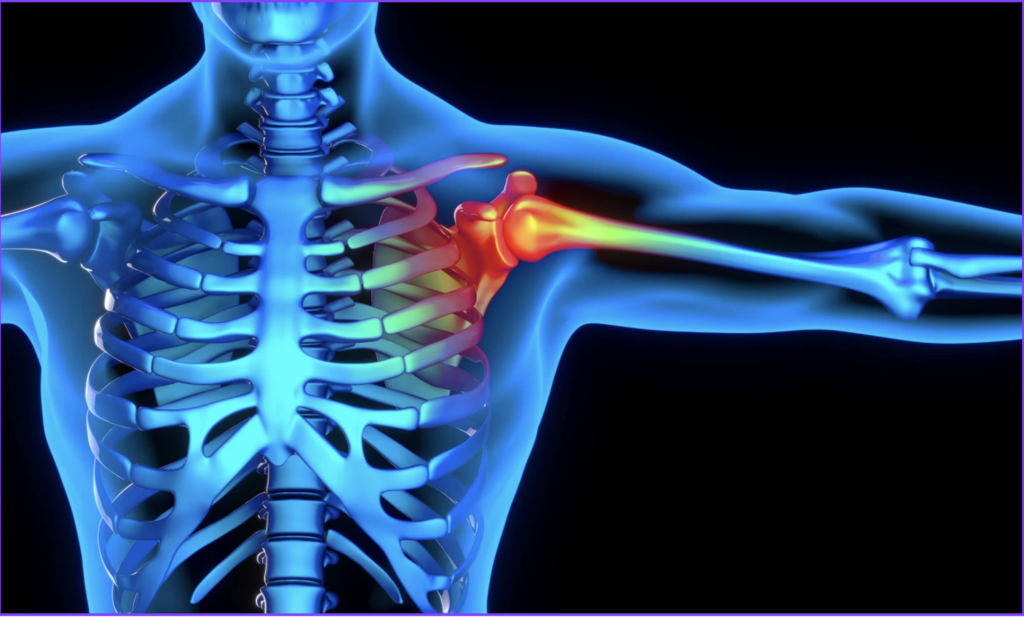

腱板断裂とは?

腱板とは、肩関節を安定させるための筋肉と腱の集まりです。この腱板が損傷・断裂することで、

・腕が上がらない

・力が入りにくい

・動かすと痛い

といった症状が現れます。

腱板断裂の特徴

・腕を上げる力が入りにくい

・特定の角度で力が抜けたり、痛みがでる

・他動では動くが自動挙上が困難なことがある